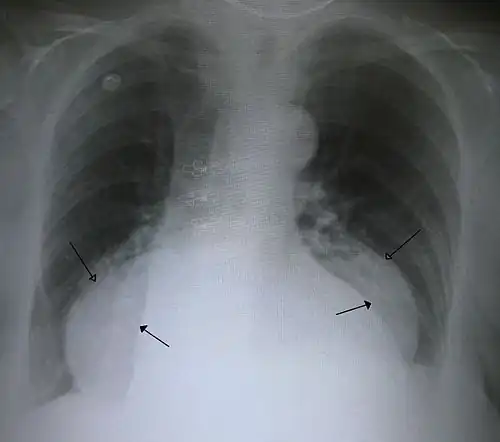

Type III: Type III hernias have elements of both types I and II hernias. With progressive enlargement of the hernia through the hiatus, the phrenoesophageal ligament stretches, displacing the gastroesophageal junction above the diaphragm, thereby adding a sliding element to the type II hernia.

Type IV: Type IV hiatus hernia is associated with a large defect in the phrenoesophageal ligament, allowing other organs, such as the colon, spleen, pancreas, and small intestine to enter the hernia sac.

The end stage of type I and type II hernias occurs when the whole stomach migrates up into the chest by rotating 180° around its longitudinal axis, with the cardia and pylorus as fixed points. In this situation, the abnormality is usually referred to as an intrathoracic stomach.

The diagnosis of a hiatal hernia is typically made through an upper GI series, endoscopy, high resolution manometry, esophageal pH monitoring, and computed tomography (CT). Barium swallow, as in the upper GI series, allows the size, location, stricture, and stenosis of oesophagus to be seen. It can also evaluate the oesophageal movements. Endoscopy can analyse the esophageal internal surface for erosions, ulcers, and tumours.

Meanwhile, manometry can determine the integrity of esophageal movements and the presence of esophageal achalasia. pH testing allows the quantitative analysis of acid reflux episodes. A CT scan is useful in diagnosing complications of hiatal hernia, such as gastric volvulus, perforation, pneumoperitoneum, and pneumomediastinum.[8]